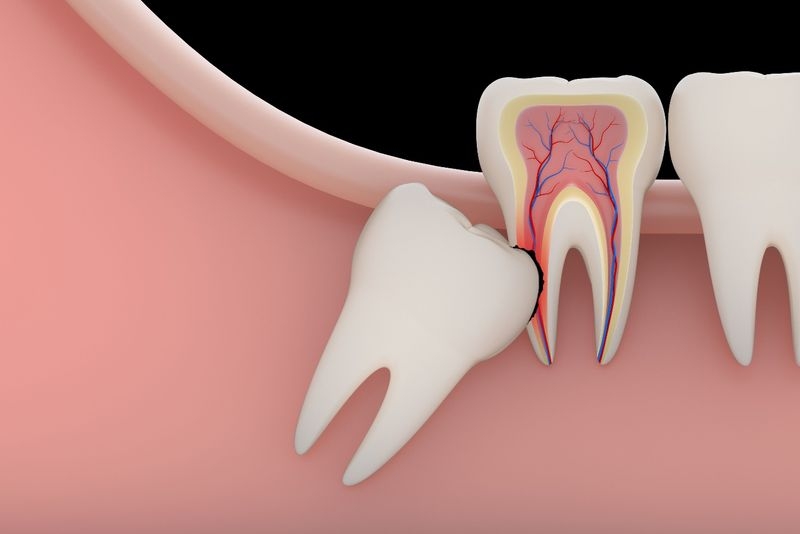

Răng mọc ngầm là tình trạng răng nằm sâu bên trong ổ xương hàm hoặc nằm ngay dưới nướu nhưng nó lại không thể tách nướu ra và trồi lên được. Răng ngầm có thể gặp ở cả hai hàm trên và dưới, đặc biệt là răng nanh và các răng số 8 bởi vì nó thường mọc muộn nên thiếu khoảng trống cho răng mọc lên.

Tình trạng răng mọc ngầm là một trong những nguyên nhân hàng đầu gây ảnh hưởng tới sức khỏe cũng như thẩm mỹ của răng miệng. Nghiêm trọng hơn thế, răng mọc ngầm còn làm tăng nguy cơ mắc bệnh lý răng miệng, đồng thời nó cũng ảnh hưởng đến các răng kế cận và làm tổn thương thần kinh.

Nhổ răng mọc ngầm có nguy hiểm không, khi nào cần nhổ Răng mọc ngầm là gây ảnh hưởng tới sức khỏe cũng như thẩm mỹ của răng miệng